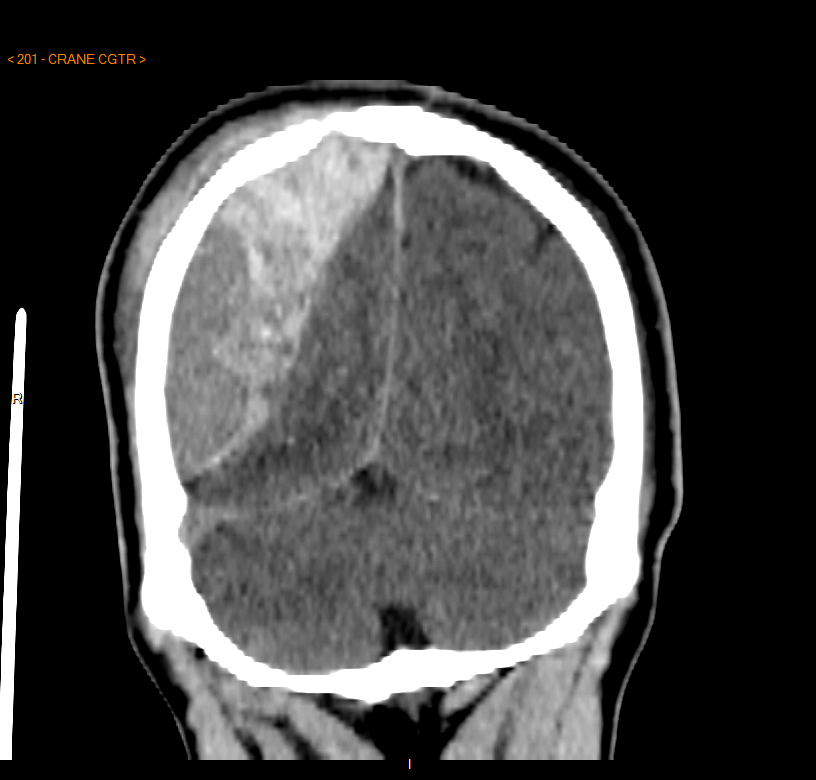

1- Hier: 14ans chute de vélo non casqué

https://abs.twimg.com/emoji/v2/... draggable="false" alt="💀" title="Schädel" aria-label="Emoji: Schädel"> dans les escaliers, trauma crânien sans perte de connaissance...

Quelques heures après violents maux de tête, vomissements, somnolence

Hospitalisé GRATUITEMENT aux URGENCES pour scanner:

- fracture du crâne

- gros hématome extradural